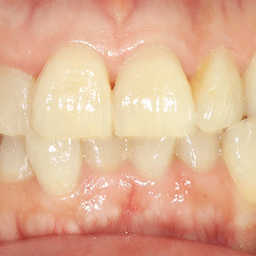

앞니 크라운

Before

After

외상으로 파절된 앞니를 자연스럽게 복원